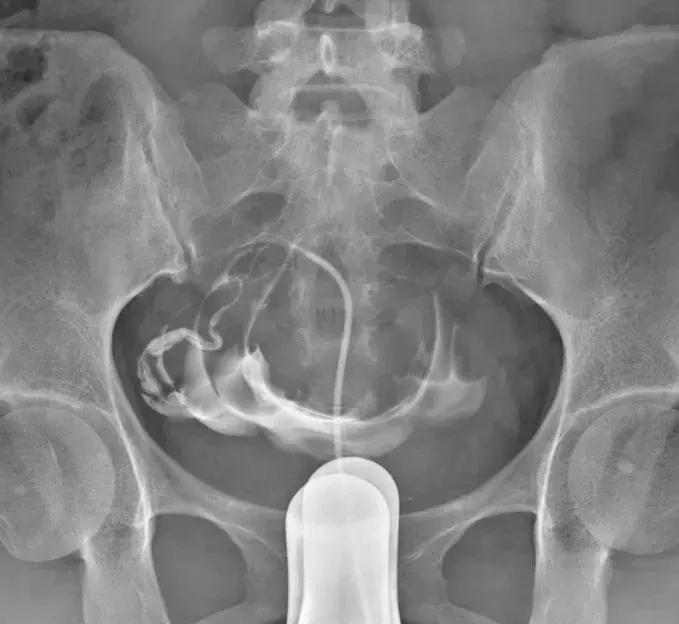

1、输卵管介入治疗

这个治疗是通过造影剂和通液药物溶液(有抗炎和防止粘连作用)的流体压力对输卵管管腔产生挤压、分离,从而避免了假性堵塞的现象,对不能完全复通的输卵管再行导丝介入。简单地讲,就是用液体和导丝去疏通输卵管管腔,就像捅下水道一样。

适用情况:通而及不畅和基本不通或堵塞的时候,可以考虑尝试这个方法。

弊端:只能解决输卵管管腔里面的问题,如果是因为输卵管表面黏连扭曲,引起的不通,是没有办法的。该治疗方案对于粘连可能有一定的疏通作用,但是导丝退出后,常常粘连恢复,这也就大家尝试的治疗没有效果,怎么办呢?这就要看手术医生的操作手法与后期的药物治疗。

优点:价格稍微便宜,几千元左右。门诊治疗不用住院,时间较短。

SSG是门诊操作的,需要X光透视,所以没有办法联合同时手术。